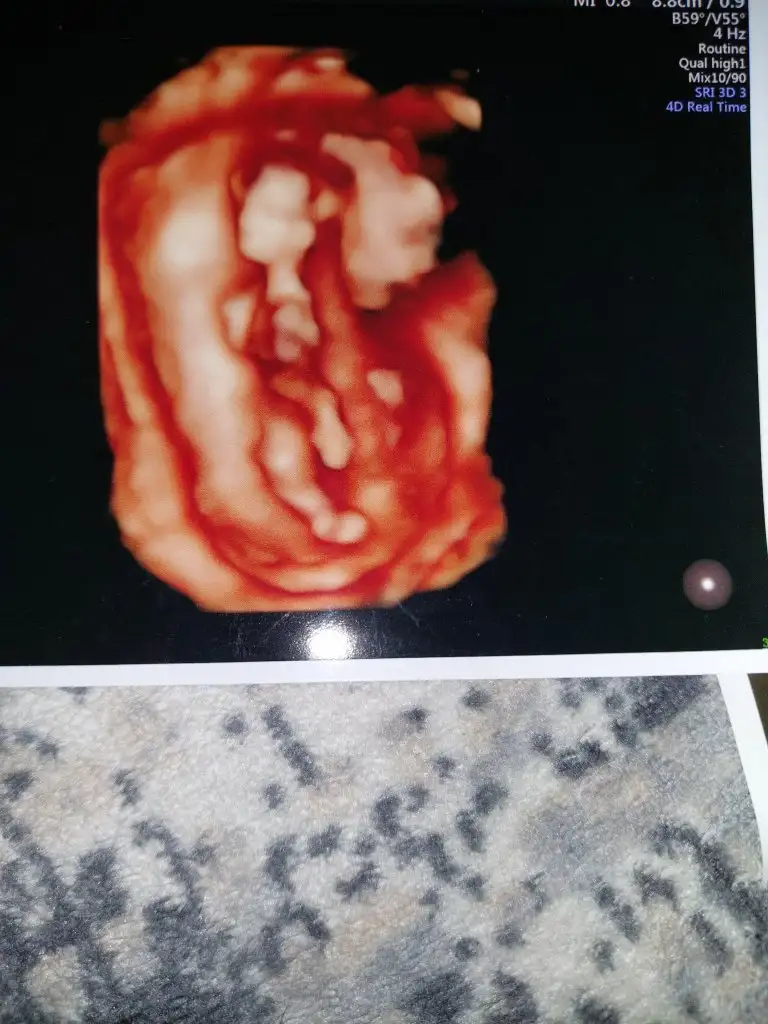

kuzum buna tahminde bulunamadım, 6 haftalıkkrb yolk kesen görünüyor zaten diğerinde de bebek üstü yazılarla kapalıCanım benim de 6 haftalıkken bu ultrasonum yorum yapabilir misin diğeri 8 haftalıktı

Tamam canım teşekkürler.kuzum buna tahminde bulunamadım, 6 haftalıkkrb yolk kesen görünüyor zaten diğerinde de bebek üstü yazılarla kapalı

kuzum prenses gibi duruyorEki Görüntüle 3042580 Eki Görüntüle 3042581 Eki Görüntüle 3042582